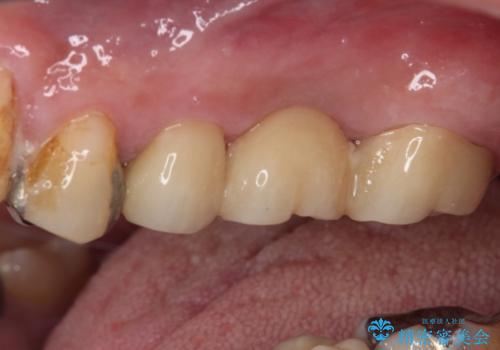

上顎の歯根のみとなった歯は抜歯が必要であったので、抜歯を行い、インプラントあるいはブリッジのよる補綴治療を提案しました。

前後の歯は銀歯が装着されていたため、ブリッジによる補綴治療として、前後の歯もセラミックに置き換えることとしました。

歯根のみとなっていた上顎の歯は、そのうち治療すれば残せるであろうと思っていたようですが、どこの歯医者に相談しても抜歯と言われたため、抜歯することとしたようです。

むし歯は放置して改善することはあり得ませんので、早めの処置が大切です。